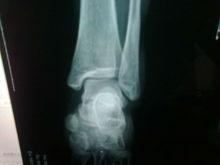

骨頭錯位● 及時檢查扭傷嚴重不妨對關節做x光照像檢查,因為嚴重扭傷與骨折經常不易區分。如確診,可在扭傷的肢體或手指部位鑄敷石膏模。

骨折的錯位可以因暴力的大小不同和作用方向的不同而發生多種移位,如發生成角、短縮、側方和鏇轉的移位,有的可以是單一種的移位,也可以是多種的移位。在下肢如發生短縮的移位,就可出現下肢的不等長;發生鏇轉的移位,在骨折癒合後,會發生走路時內或外八字的步態。